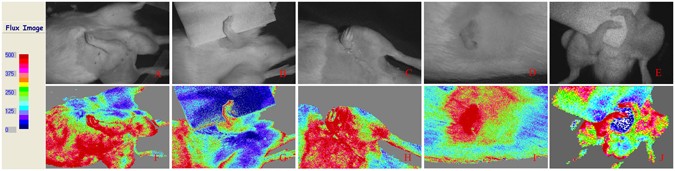

The contrast images were processed to produce a color-coded live flux image (Fig. 4; the red color represented high flow speed and perfusion, and blue denoted low flow speed and perfusion). All amputated limbs denoted red color, thus representing high flow speed and perfusion with high BPU value of more than 400.

BPU of FLPI showed good blood supply to amputated limbs of different ectopic implantation models in rats. (A) Forelimb ectopic implantation (B) forearm ectopic implantation (C) forepaw ectopic implantation (D) first digit ectopic implantation (E) double forelimbs ectopic implantation.